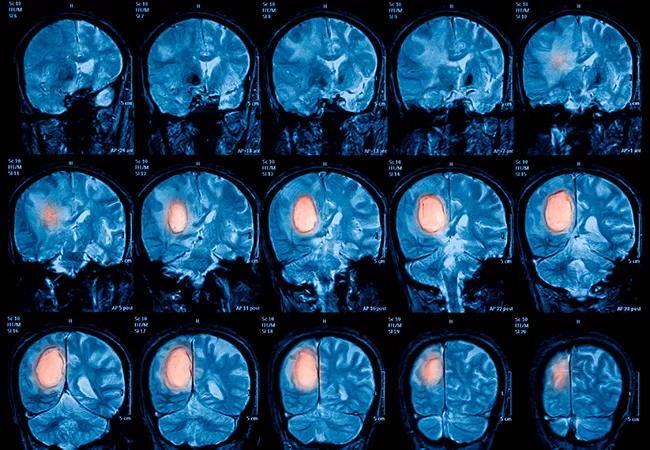

Magnetic resonance imaging (MRI) of the brain, brain tumor

A study conducted in 22 adult patients with low-grade glioma found that concurrent temozolomide-based chemoradiation therapy does not adversely influence neurocognitive function during a 2-year treatment follow up. Cleveland Clinic investigator Erin S. Murphy, MD presented the early findings of this collaborative research at the American Society for Radiation Oncology (ASTRO) 2021 Annual Meeting held in Chicago on October 24-27, 2021.